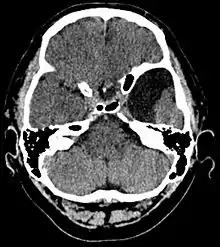

الكيسات العنكبوتية (بالإنجليزية: Arachnoid cysts) هي عبارة عن سائل دماغي شوكي مغطى بالخلايا العنكبوتية والكولاجين[1] والذي قد ينمو بين سطح الدماغ وقاعدة الجمجمة أو على الغشاء العنكبوتي، وهو أحد الطبقات السحائية الثلاث التي تغطي الدماغ والحبل الشوكي.[2] وتُعد الكيسات العنكبوتية الأولية هي اضطراب خلقي بينما الكيسات العنكبوتية الثانوية هي نتيجة لإصابة في الرأس أو صدمة.[3] تبدأ معظم حالات الكيسات الأولية خلال فترة الرضاعة؛ ومع ذلك قد يتأخر ظهورها حتى سن المراهقة.

![]() صورة بالرنين المغناطيسي لامراة تبلغ من العمر 25عامًا مصابة بكيسة عنكبوتية جبهية صدغية يسري. صورة بالرنين المغناطيسي لامراة تبلغ من العمر 25عامًا مصابة بكيسة عنكبوتية جبهية صدغية يسري. | |